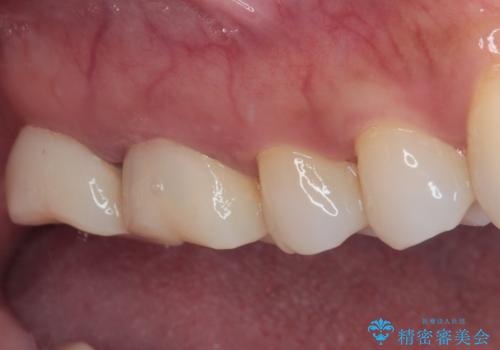

歯周外科処置を併用した奥歯のむし歯治療

隣接する部分の間のむし歯が歯肉の奥深くにまで及んでおり、歯肉が腫れやすい状態となっていたため、歯肉の切除並びに歯槽骨の形態修正を行い、虫歯が歯肉の外に出てくるようにした上で、オールセラミックにて補綴することとしました。

歯間ブラシを通す度に出血をするのは、ご自身の磨き方が悪いからと思っていらっしゃいましたが、治療後は全く出血することがなくなり、患者様には大変満足していただきました。